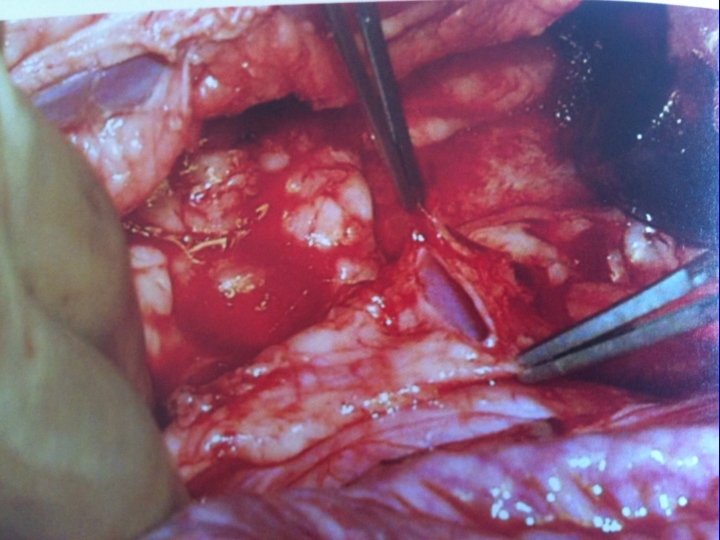

Boari flap

Small Bowel Interposition